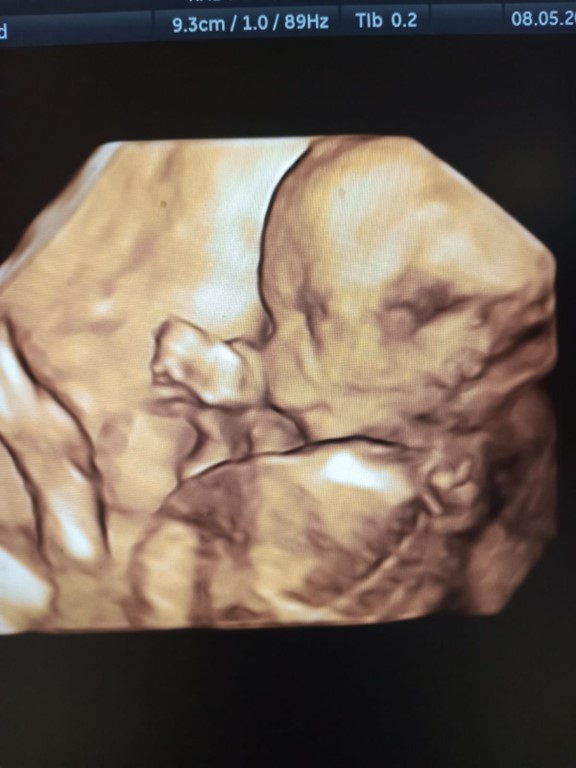

"Goedemorgen, ik heb de kinderwagen, het badje en het bedje ontvangen. Alles is perfect. Heel erg bedankt dat je me gered hebt en vooral dat je me begeleid hebt op deze zwangerschapsreis. Jouw gesprekken en de emotionele steun die je me gaf, hebben mijn ziel gered. In de eerste maanden van de zwangerschap hielp je me om moedig voor het leven te kiezen en geen abortus te laten plegen. Ik heb geen woorden om te beschrijven hoe dankbaar ik jullie ben. Ik wens iedereen die in de non-profit werkt het allerbeste. Jullie doen engelenwerk en ik had het gevoel dat God jullie als een wonder naar mij heeft gestuurd. Bedankt voor de enorme opwinding in mijn hart om te weten dat er zoveel goeds is in de wereld. Hier is de foto van mijn prachtige baby."